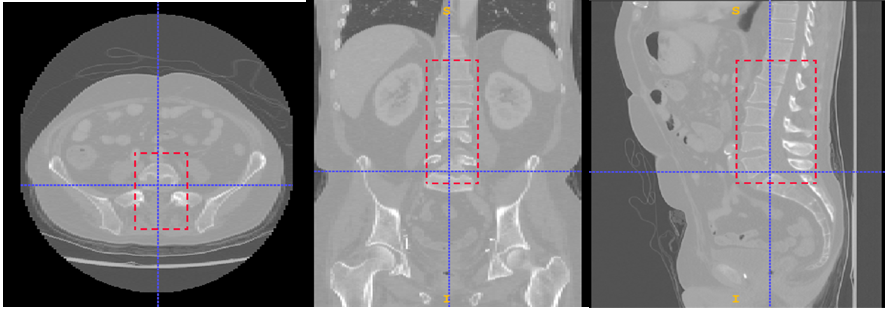

3.2.2 Annotation

The annotation process using ITK-SNAP in the three planes is illustrated in Fig 1 for creating a 3D bounding box around a lumbar spine region. The annotations of spleen, left and right kidneys are illustrated by Figures 2, 3 and 4 respectively.